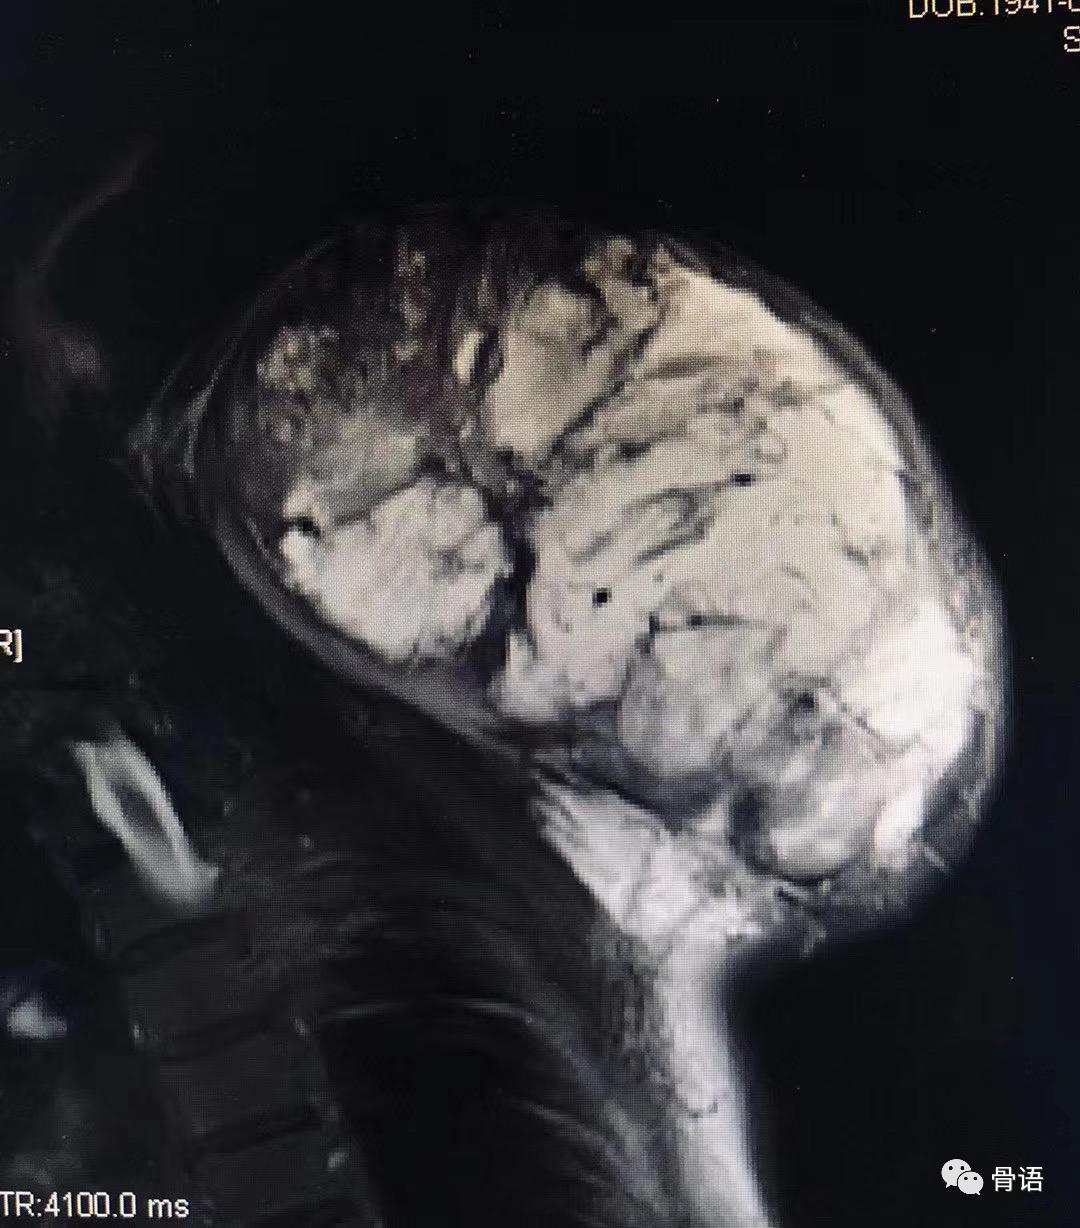

图3,图4.术前影像学检查见肩胛骨巨大软骨肉瘤。

Fig3,Fig4.Preoperative imaging examination revealed a massive chondrosarcoma of the scapula.